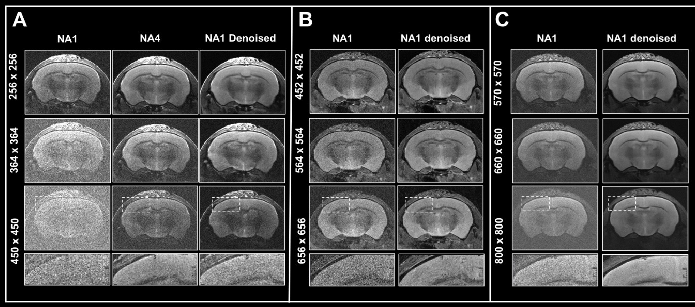

To test the denoising algorithm’s performance with images of different levels of tissue contrast, ex vivo data of a fixed mouse brain was obtained with a nominal voxel size of 55 x 55 x 800 µm3 at 3 Tesla, either without any averaging or 4 or 15 averages (as shown in Fig. 3).

This equates to a contrast-to-noise ratio between the corpus callosum and cortex of 2.47±0.45, 4.59±0.01, and 12.03±0.81, respectively. Images were reconstructed both without and with 70% and 100% denoising.

Given the somewhat high resolution, the image without averaging shows low tissue contrast and contains noise that can be reduced via averaging during acquisition or with denoising during image reconstruction. Yet, comparing obtained denoised images with different averages shows that denoising can increase spurious contrast in cases with low tissue contrast, i.e., no averaging, such as in Fig. 3, arrow.

Figure 3. Denoising images with low tissue contrast. A) Axial T2-weighted TurboRARE images of a fixed mouse head were acquired at 3 Tesla with 1, 4 and 15 number of averages (NA), respectively. Images have a nominal voxel resolution of 55 x 55 x 800 μm3. Image reconstruction was performed without (Source) and with 70% and 100% denoising. Each denoised image was reconstructed with a network Strong and a pre-denoising of 50% was applied. The arrows point to a structure in the NA1 images, that is faintly visible in the image that has not been denoised and that becomes more apparent with increasing denoising. The arrowheads point to the corpus callosum which becomes more visible. Resolution of fine structure requires high tissue contrast with averaging. Image Credit: Bruker BioSpin Group

This structure, which is faintly visible in the noisy image without denoising but not easily distinguished from the surrounding tissue, is enhanced by heightening levels of denoising. Comparing images using different averaging levels shows that with denoising, the corpus callosum becomes more visible (as shown in Fig. 3, arrowheads). However, resolving the fine structures of the corpus callosum’s limits necessitates high tissue contrast with averaging. If this is provided, denoising can enhance the visualization.